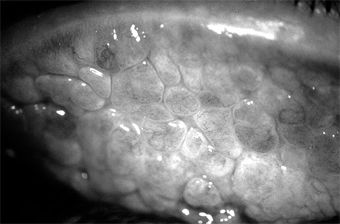

Chapter 5: Conjunctiva IMMUNOLOGIC (ALLERGIC) CONJUNCTIVITIS IMMEDIATE HUMORAL HYPERSENSITIVITY REACTIONS 1. HAY FEVER CONJUNCTIVITIS A mild, nonspecific conjunctival inflammation is commonly associated with hay fever (allergic rhinitis). There is usually a history of allergy to pollens, grasses, animal danders, etc. The patient complains of itching, tearing, and redness of the eyes and often states that the eyes seem to be "sinking into the surrounding tissue." There is mild injection of the palpebral and bulbar conjunctiva, and during acute attacks there is often severe chemosis (which no doubt accounts for the "sinking" description). There may be a small amount of ropy discharge, especially if the patient has been rubbing the eyes. Eosinophils are difficult to find in conjunctival scrapings. A papillary conjunctivitis can occur if the allergen persists (Figure 5-10). Treatment consists of the instillation of local vasoconstrictors during the acute phase (epinephrine, 1:1000 solution applied topically, will relieve the chemosis and symptoms within 30 minutes). Cold compresses are helpful to relieve itching, and antihistamines by mouth are of some value. The immediate response to treatment is satisfactory, but recurrences are common unless the antigen is eliminated. Fortunately, the frequency of the attacks and the severity of the symptoms tend to moderate as the patient ages. 2. VERNAL KERATOCONJUNCTIVITIS This disease, also known as "spring catarrh" and "seasonal conjunctivitis" or "warm weather conjunctivitis," is an uncommon bilateral allergic disease that usually begins in the prepubertal years and lasts for 5-10 years. It occurs much oftener in boys than in girls. The specific allergen or allergens are difficult to identify, but patients with vernal keratoconjunctivitis usually show other manifestations of allergy known to be related to grass pollen sensitivity. The disease is less common in temperate than in warm climates and is almost nonexistent in cold climates. It is almost always more severe during the spring, summer, and fall than in the winter. It is most commonly seen in sub-Saharan Africa and the Middle East. The patient usually complains of extreme itching and a ropy discharge. There is often a family history of allergy (hay fever, eczema, etc) and sometimes in the young patient as well. The conjunctiva has a milky appearance, and there are many fine papillae in the lower tarsal conjunctiva. The upper palpebral conjunctiva often has giant papillae that give a cobblestone appearance (Figure 5-11). Each giant papilla is polygonal, has a flat top, and contains tufts of capillaries. A stringy conjunctival discharge and a fine, fibrinous pseudomembrane (Maxwell-Lyons sign) may be noted, especially on the upper tarsus on exposure to heat. In some cases, especially in persons of black African ancestry, the most prominent lesions are located at the limbus, where gelatinous swellings (papillae) are noted. A pseudogerontoxon (arcus-like haze) is often noted in the cornea adjacent to the limbal papillae. Trantas' dots are whitish dots seen at the limbus in some patients with vernal keratoconjunctivitis during the active phase of the disease. Many eosinophils and free eosinophilic granules are found in Giemsa-stained smears of the conjunctival exudate and in Trantas' dots. Micropannus is often seen in both palpebral and limbal vernal keratoconjunctivitis, but gross pannus is unusual. Conjunctival scarring usually does not occur unless the patient has been treated with cryotherapy, surgical removal of the papillae, irradiation, or other damaging procedure. Superficial corneal ("shield") ulcers (oval and located superiorly) may form and may be followed by mild corneal scarring. A characteristic diffuse epithelial keratitis frequently occurs. None of the corneal lesions respond well to standard treatment. The disease may be associated with keratoconus. Treatment Since vernal keratoconjunctivitis is a self-limited disease, it must be recognized that the medication used to treat the symptoms may provide short-term benefit but long-term harm. Topical and systemic steroids, which relieve the itching, affect the corneal disease only minimally, and their side effects (glaucoma, cataract, and other complications) can be severely damaging. Topical cromolyn is a useful prophylactic agent in moderate to severe cases. Vasoconstrictors, cold compresses, and ice packs are helpful, and sleeping (if possible, also working) in cool, air-conditioned rooms can keep the patient reasonably comfortable. Probably the best remedy of all is to move to a cool, moist climate. Patients able to do so are benefited if not completely cured. The severe symptoms of an extremely photophobic patient who is unable to function can often be relieved by a short course of topical or systemic steroids followed by vasoconstrictors, cold packs, and regular use of histamine-blocking agents as eyedrops. Newer nonsteroidal anti-inflammatory medications, including ketorolac and lodoxamide, may provide significant symptomatic relief. (See discussion in Chapter 3.) As has already been indicated, the prolonged use of steroids must be avoided since it is all too often followed by herpes simplex keratitis, cataract, glaucoma, and fungal and other opportunistic corneal ulcers. Recent clinical studies have shown that topical 2% cyclosporine eye drops are effective in severe unresponsive cases. Supratarsal injection of depot corticosteroids has been demonstrated to be effective for vernal shield ulcers. Desensitization to grass pollens and other antigens has not been rewarding. Staphylococcal blepharitis and conjunctivitis are frequent complications and should be treated. Recurrences are the rule, particularly in the spring and summer; but after a number of recurrences the papillae disappear completely, leaving no scars. 3. ATOPIC KERATOCONJUNCTIVITIS Patients with atopic dermatitis (eczema) often also have atopic keratoconjunctivitis. The symptoms and signs are a burning sensation, mucoid discharge, redness, and photophobia. The lid margins are erythematous, and the conjunctiva has a milky appearance. There are fine papillae, but giant papillae are less developed than in vernal keratoconjunctivitis and occur more frequently on the lower tarsus-unlike the giant papillae of vernal keratoconjunctivitis, which are on the upper tarsus (Figure 5-12). Severe corneal signs appear late in the disease after repeated exacerbations of the conjunctivitis. Superficial peripheral keratitis develops and is followed by vascularization. In severe cases, the entire cornea becomes hazy and vascularized, and visual acuity is reduced. The disease may be associated with keratoconus. There is usually a history of allergy (hay fever, asthma, or eczema) in the patient or the patient's family. Most patients have had atopic dermatitis since infancy. Scarring of the flexure creases of the antecubital folds and of the wrists and knees is common. Like the dermatitis with which it is associated, atopic keratoconjunctivitis has a protracted course and is subject to exacerbations and remissions. Like vernal keratoconjunctivitis, it tends to become less active when the patient reaches the fifth decade. Scrapings of the conjunctiva show eosinophils, though not nearly as many as are seen in vernal keratoconjunctivitis. Scarring of both the conjunctiva and cornea is often seen, and an atopic cataract, a posterior subcapsular plaque, or an anterior shield-like cataract may develop. Keratoconus, retinal detachment, and herpes simplex keratitis are all more than usually frequent in patients with atopic keratoconjunctivitis, and there are many cases of secondary bacterial blepharitis and conjunctivitis, usually staphylococcal. The management of atopic keratoconjunctivitis is often discouraging. Any secondary infection must be treated. Environmental control should be considered. Oral antihistamines including terfenadine (60-120 mg twice daily), astemizole (10 mg four times daily), or hydroxyzine (50 mg at bedtime, increasing to 200 mg at bedtime) have been shown to be of value. Newer nonsteroidal anti-inflammatory medications, including ketorolac and lodoxamide, show promise for symptomatic relief for these patients (see Chapter 3). A short course of topical steroids may relieve symptoms. In severe cases, plasmapheresis may be an adjunct to therapy. In advanced cases with severe corneal complications, corneal transplantation may be needed to improve the visual acuity. 4. GIANT PAPILLARY CONJUNCTIVITIS Giant papillary conjunctivitis with signs and symptoms resembling those of vernal conjunctivitis may develop in patients wearing plastic artificial eyes or contact lenses. It is probably a basophil-rich delayed hypersensitivity disorder (Jones-Mote hypersensitivity), perhaps with an IgE humoral component. Use of glass instead of plastic for prostheses and spectacle lenses instead of contact lenses is curative. If the goal is to maintain contact lens wear, additional therapy will be required. Careful contact lens care, including preservative-free agents, is essential. Hydrogen peroxide disinfection and enzymatic cleaning of contact lenses may also help. Changing to a different brand or style of contact lenses may be necessary if other measures fail. If these treatments are unsuccessful, contact lenses should be discontinued. DELAYED HYPERSENSITIVITY REACTIONS 1. PHLYCTENULOSIS Phlyctenular keratoconjunctivitis is a delayed hypersensitivity response to microbial proteins, including the proteins of the tubercle bacillus, Staphylococcus species, Candida albicans, Coccidioides immitis, Haemophilus aegyptius, and Chlamydia trachomatis serotypes L1, L2, and L3. Until recently, by far the most frequent cause of phlyctenulosis in the USA was delayed hypersensitivity to the protein of the human tubercle bacillus. This is still the commonest cause in regions where tuberculosis is still prevalent. In the USA, however, most cases are now associated with delayed hypersensitivity to S aureus. The conjunctival phlyctenule begins as a small lesion (usually 1-3 mm in diameter) that is hard, red, elevated, and surrounded by a zone of hyperemia. At the limbus it is often triangular in shape, with its apex toward the cornea. In this location it develops a grayish-white center that soon ulcerates and then subsides within 10-12 days. The patient's first phlyctenule and most of the recurrences develop at the limbus, but there may also be corneal, bulbar, and, very rarely, even tarsal phlyctenules. Unlike the conjunctival phlyctenule, which leaves no scar, the corneal phlyctenule develops as an amorphous gray infiltrate and always leaves a scar. Consistent with this difference is the fact that scars form on the corneal side of the limbal lesion and not on the conjunctival side. The result is a triangular scar with its base at the limbus-a valuable sign of old phlyctenulosis when the limbus has been involved. Conjunctival phlyctenules usually produce only irritation and tearing, but corneal and limbal phlyctenules are usually accompanied by intense photophobia (Figure 5-13). Phlyctenulosis is often triggered by active blepharitis, acute bacterial conjunctivitis, and dietary deficiencies. Phlyctenular scarring, which may be minimal or extensive, is often followed by Salzmann's nodular degeneration. Histologically, the phlyctenule is a focal subepithelial and perivascular infiltration of small round cells, followed by a preponderance of polymorphonuclear cells when the overlying epithelium necrotizes and sloughs-a sequence of events characteristic of the delayed tuberculin type hypersensitivity reaction. Phlyctenulosis induced by tuberculoprotein and the proteins of other systemic infections responds dramatically to topical corticosteroids. There is a major reduction of symptoms within 24 hours and disappearance of the lesion in another 24 hours. Phlyctenulosis produced by staphylococcal proteins responds somewhat more slowly. Topical antibiotics should be added for active staphylococcal blepharoconjunctivitis. Treatment should be aimed at the underlying disease, and the steroids, when effective, should be used only to control acute symptoms and persistent corneal scarring. Severe corneal scarring may call for corneal transplantation. 2. MILD CONJUNCTIVITIS SECONDARY TO CONTACT BLEPHARITIS Contact blepharitis caused by atropine, neomycin, broad-spectrum antibiotics, and other topically applied medications is often followed by a mild infiltrative conjunctivitis that produces hyperemia, mild papillary hypertrophy, a mild mucoid discharge, and some irritation (Figure 5-14). Examination of Giemsa-stained scrapings often discloses only a few degenerated epithelial cells, a few polymorphonuclear and mononuclear cells, and no eosinophils. Treatment should be directed toward finding the offending agent and eliminating it. The contact blepharitis may clear rapidly with topical cortico-steroids, but their use should be limited. Long-term use of steroids on the lids may lead to steroid glaucoma and to skin atrophy with disfiguring telangiectasis. PREVIOUS | NEXT Page: 1 | 2 | 3 | 4 | 5 | 6 | 7 | 8 | 9 | 10 | 11 | 12 | 13 | 14 10.1036/1535-8860.ch5 |